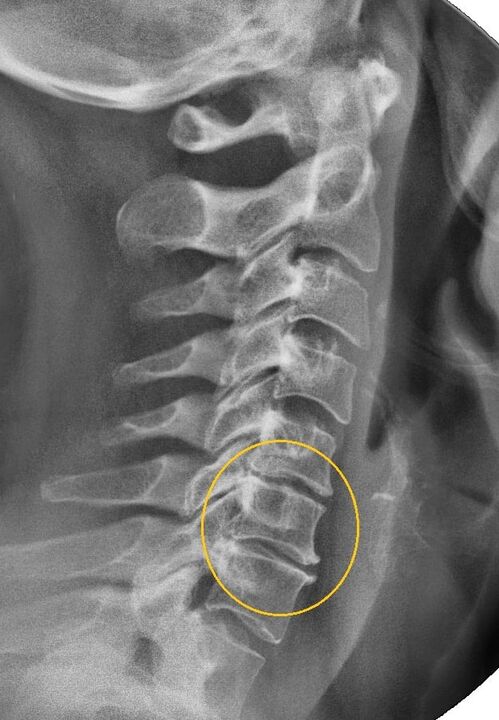

Nejinformativnějším diagnostickým postupem je radiografie. Patologie 1. stupně odpovídají 1. nebo 2. radiologickému stadiu. Výsledné snímky vizualizují typické příznaky onemocnění.

| Rentgenová stadia cervikální osteochondrózy 1. stupně | Charakteristické znaky |

|---|---|

| Fáze 1 | Drobné změny v zakřivení páteře v krční oblasti, postihující jeden nebo více segmentů |

| Fáze 2 | Mírné ztluštění meziobratlových plotének, deformace výběžků necinate, napřímení lordózy, drobné výrůstky kostních struktur |